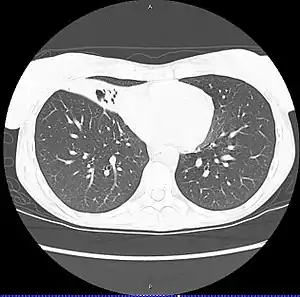

| CT scan of patient with right middle lobe aspiration and Mycobacterium avium infection consistent with Lady Windermere syndrome | |